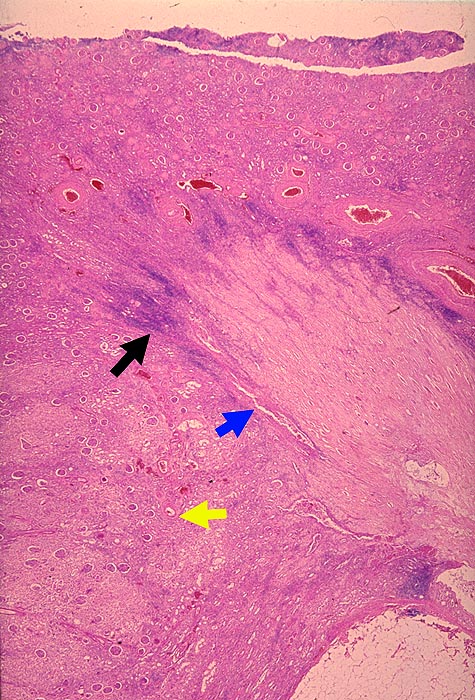

AP/ Analgetikanephropathie

Analgetikanephropathie

Niere

Morphologie